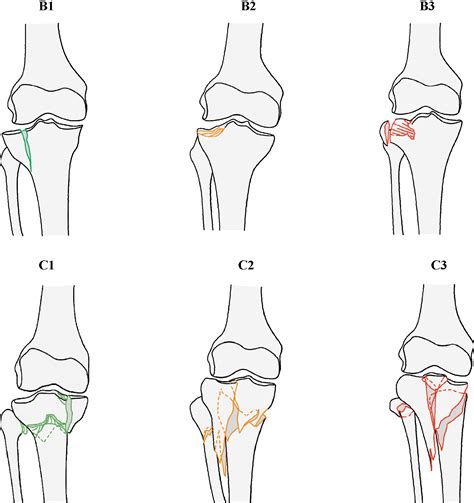

Medical professionals use the Ogden classification system to grade the severity of these fractures. Understanding the grade is essential for determining whether conservative management or surgery is required. The system is categorized based on the displacement of the bone fragment and the extent of the damage to the growth plate.

Type Description

Type I Fracture occurs at the distal part of the tibial tubercle; displacement is minimal.

Type II Fracture extends through the secondary ossification center; typically involves more displacement.

Type III Fracture extends through the articular surface of the knee joint.

Type IV Fracture extends posteriorly through the entire proximal tibial metaphysis.

💡 Note: Higher-grade injuries (Type III and IV) almost always necessitate surgical intervention to ensure the smooth surface of the knee joint is restored and future mobility is not compromised.